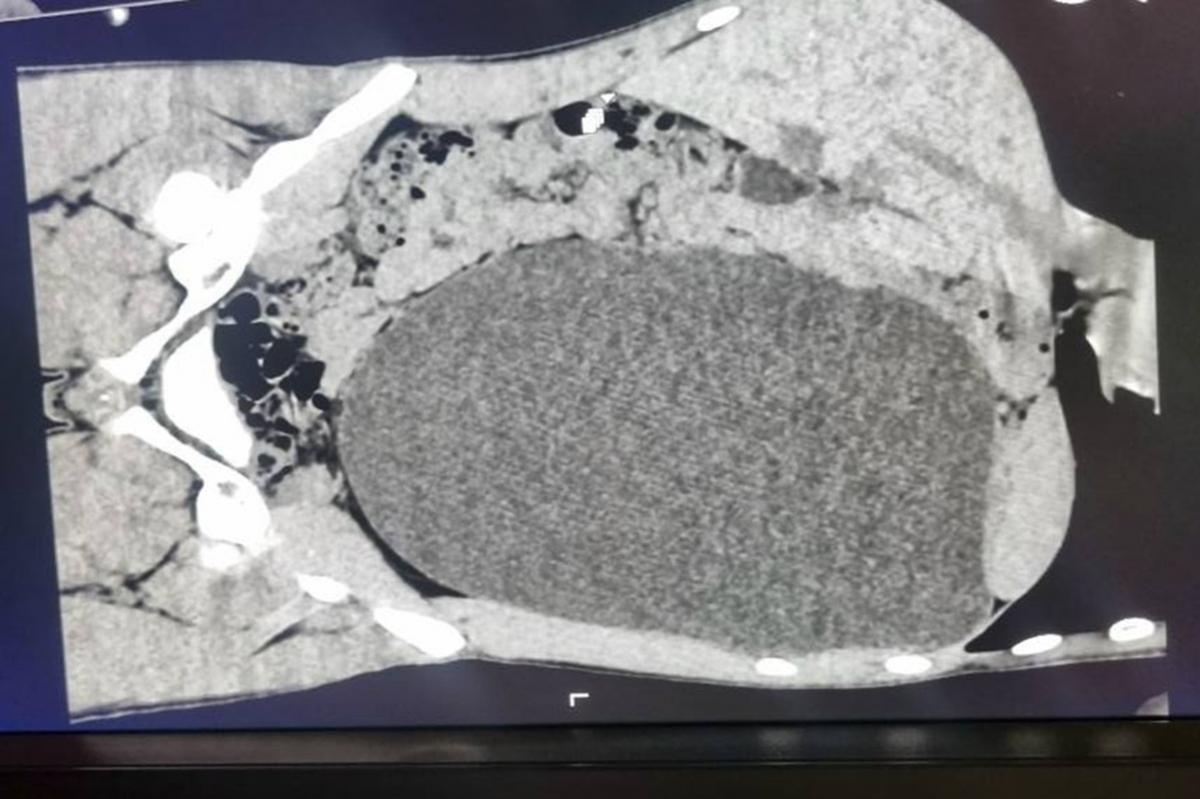

Плановый медосмотр перед устройством на работу спас жизнь 17-летнему новосибирцу. Во время УЗИ врачи обнаружили у юноши огромное образование в брюшной полости. Как выяснилось позже, это была левая почка, пораженная гидронефрозом — она раздулась до размеров пятилитровой бутыли и почти полностью утратила функциональную ткань.

«У нашего пациента почка достигла размеров пятилитровой бутылки! Она занимала почти весь объем живота и давила на все соседние органы. Это была настоящая "бомба замедленного действия": любая травма, случайный удар в живот — и мешок мог разорваться внутри», — рассказали в детской горбольнице №1.